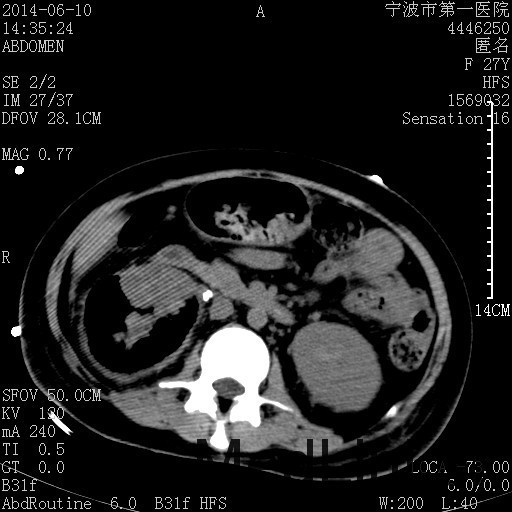

诊断为“气性肾盂肾炎,感染性休克,糖尿病酮症酸中毒” 血、尿、脓液培养均示“克雷伯杆菌” 入院第2天行“右双J管置入术” 入院第3天、7天行“右肾穿刺造瘘术” 入院1月行“右肾切除术” 术后顺利康复出院。

气性肾盂肾炎 • 气性肾盂肾炎是产气尿路病原体引起的急性肾实质坏死和肾周感染 • 大肠杆菌是最常见的病原菌,其次是克雷伯杆菌和变形杆菌 • 绝大多数气性肾盂肾炎患者合并糖尿病 • 死亡率19%至43%,单独的内科治疗通常是致命的,大部分患者最终需要行肾切除术 下一步治疗方案 • 拟行右肾切除术 • 患者经充分引流、抗感染治疗后现病情平稳,血糖控制良好 • 感染灶范围大,不能通过保守治疗消除,以往经验告诉我们保守治疗效果往往不佳 • 长期抗生素应用易引起真菌感染、伪膜性肠炎等并发症 • 若细菌对泰能耐药,后续抗感染治疗将十分困难 术前评估 • 手术风险评估(NNIS分级 2~3分) – IV 类手术切口(1分) – P3有严重系统性疾病,日常活动受限,但未丧失工作能力(1分) – T1手术在3小时内完成(0~1分) – 营养危险评分(NRS-2002) 营养状态评分3分+疾病严重程度评分2分=5分 围手术期治疗 • 术前、术中、术后血糖控制和调整 • 术后重症监护支持 • 感染控制和抗生素使用 • 手术前麻醉准备 患者最终在入院后1月行右肾切除术,术后康复出院。